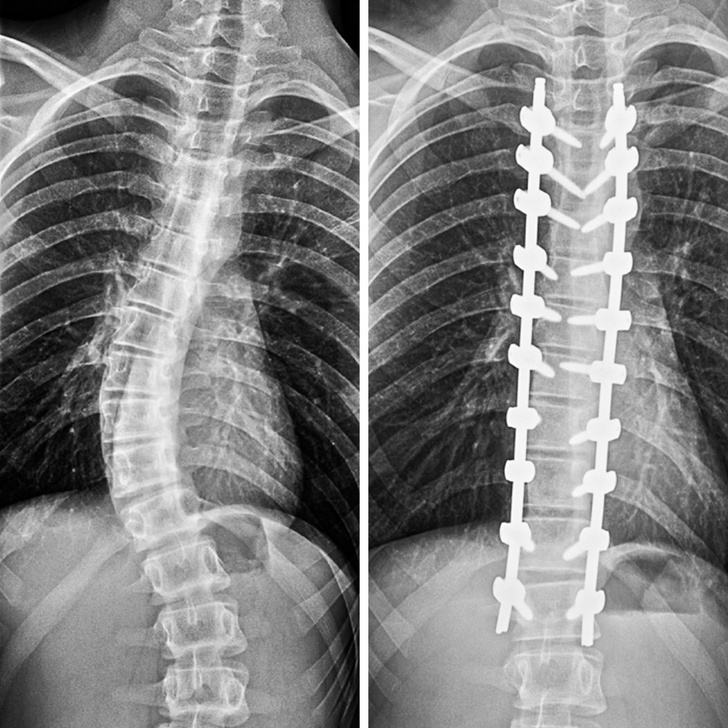

3. ,,Így néz ki a gerincem a gerincferdülést korrigáló műtétem után.”